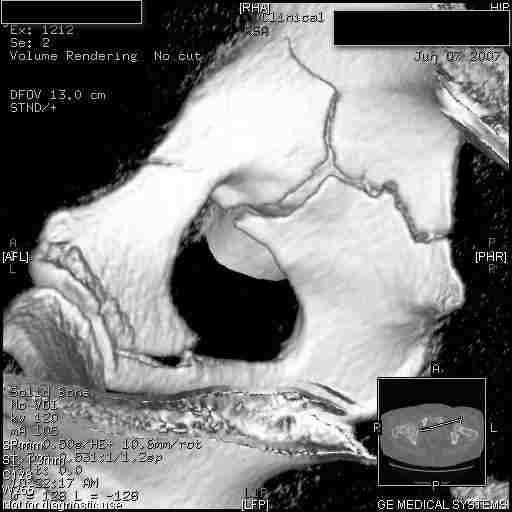

Следом 3d

Приветствую,Антон.Рункова рядом нет,но после полученных данных КТ,обсуждали совместно.Итог обсуждения-развернутый ответ дать не получится,т.к.срезы выбраны не информативные.Если ориентироваться на данные 3D,то ,ИМХО,можно лечить на вытяжении.

Спасибо, Салават и коллеги. Насколько я понял,нужны срезы в сагитальной и фронтальной плоскостях?